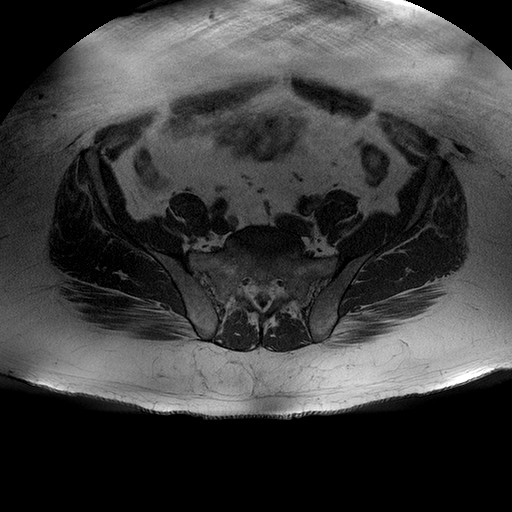

Esami: RMN BACINO

T1W_TSE

Evidenti e simmetriche alterazioni osteofitosiche in regione coxo femorale con riduzione delle rime articolari. Degenerazione completa del cercine glenoideo. Non attuali segni di versamento articolare. Non segni di edema osseo che escludono attuale algodistrofia od osteonecrosi. Lieve e simmetrica riduzione del trofismo della muscolatura glutea.